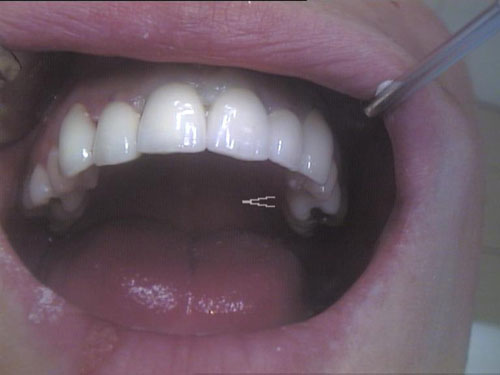

Zahn-Anomalien 1

Zahn-Anomalien 2

Zahn-Anomalien 3

Zahn-Anomalien 4

Zahn-Anomalien 5